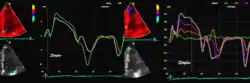

Spectral tissue velocity curves from the mitral annulus at the septal (left) and lateral (right) points. The curves show multiple heartbeats.

Pulsed wave spectral tissue Doppler has become a universal tool that is part of the general echocardiographic examination. Like any other echocardiographic measurement, measures by tissue Doppler should be interpreted in the context of the whole examination. The velocity curves are in general taken from the base of the mitral annulus at the insertion of the mitral leaflets, in the septal and lateral points of the four chamber view, and eventually the anterior and inferior points of the two-chamber views. For the right ventricle it is customary to use the lateral point of the tricuspid annulus only. Averaging peak velocities from the septal and lateral point has become common, although it has been shown that averaging all four points mentioned above, gives significantly less variability[3]

The method measures annular velocities to and from the probe during the heart cycle.

Single spectral tissue velocity curve from the mitral annulus. The curve shows velocities towards the probe (positive velocity) in systole, and away from the probe (negative velocities) in diastole. The most useful measures are the peak velocities, in systole S' and in early diastole (e') and late diastole during atrial contraction (a').

Annular velocities summarize the longitudinal contraction of the ventricle during systole, and elongation during diastole. Peak velocities are commonly used.